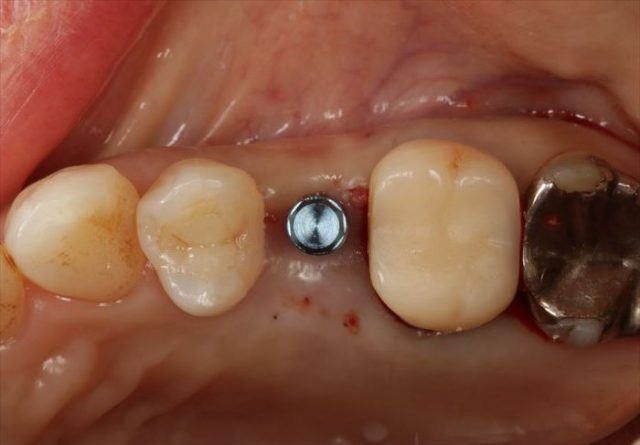

挿入ジグを外しました。

封鎖スクリューでインプラントフィクスチャーを保護します。

フラップレス埋入オペでは出血もあまりありません。

無事に終わりました。